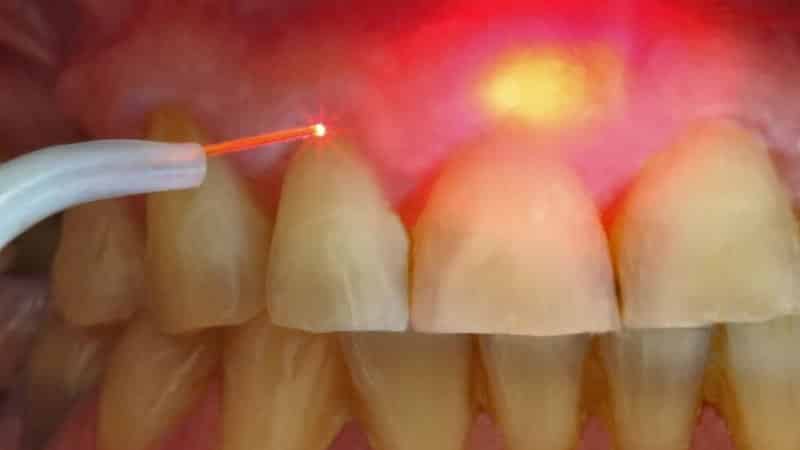

С целью сокращения хирургических процедур, пациентам вначале назначается рентгенологическое исследование и компьютерная томография. По результатам этих исследований определяется место образования и его связь с корневой системой. В процессе лечения проводится обработка каналов специальными инструментами, лазером, медикаментозное лечение, а иногда применяется озонотерапия. После достижения положительного результата проводится пломбирование.

Сегодняшним эффективным методом лечения является использование лазера. Этот метод позволяет сохранить зуб без повреждений, что является его преимуществом перед другими процедурами. Лазерная технология включает несколько этапов: вскрытие или распломбирование зуба, расширение корневых каналов, введение лазера и уничтожение вредных микроорганизмов и удаление кисты лазерным лучом. Лазерное лечение обладает особым преимуществом в виде дезинфекции пораженных тканей, предотвращая осложнения и способствуя быстрому заживлению. Эта процедура считается безболезненной и оперативной, что приятно для пациентов. Если через полгода после лечения киста челюсти не проявляет симптомов, то дальнейшие меры не требуются, возможно, это была гранулема. Однако, если воспалительный процесс продолжается, пациент направляется к хирургу для полного удаления.